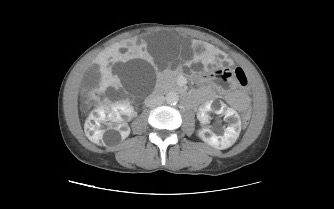

Ampliación del estudio: TAC abdominal

Debido a la presencia del quiste hepático de aspecto atípico, el especialista decide ampliar el estudio mediante TAC abdominal.

En los cortes axiales y coronales se observa con claridad:

- Múltiples quistes en el parénquima hepático

- Quistes renales bilaterales

- La lesión hepática previamente descrita

El TAC permite confirmar la extensión hepatorrenal de la enfermedad y caracterizar mejor las lesiones.